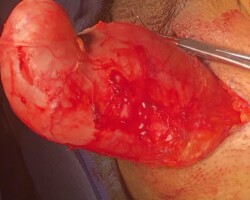

Resection of large retroperitoneal sarcoma including right and transverse colectomy and right hepatectomy